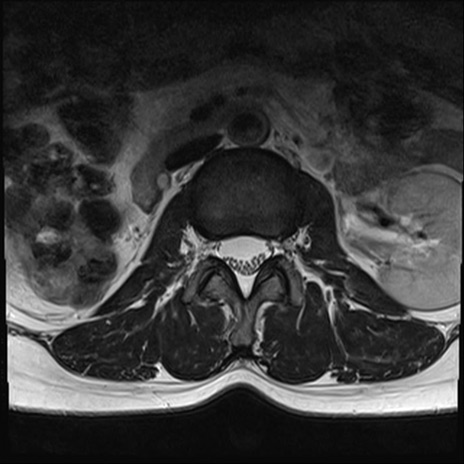

【整形】TIPS症例4 腰椎MRI T2WI(横断像)

腰椎MRI

横断像と矢状断像